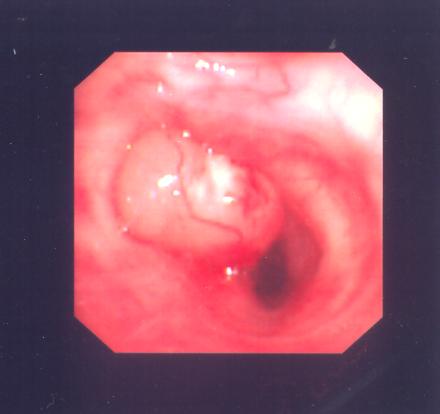

Flexible bronchoscopy on 28 Jan 2010 showed her LB6 was obstructed by a cystic mass ( fig.1) . Bronchial aspirate was negative for acid fast bacilli and malignancy. Biopsy was not taken because of the suspicion of carcinoid tumour.

Fig. 1 (Above) Patient 1 with LB6 obstructed by a mass